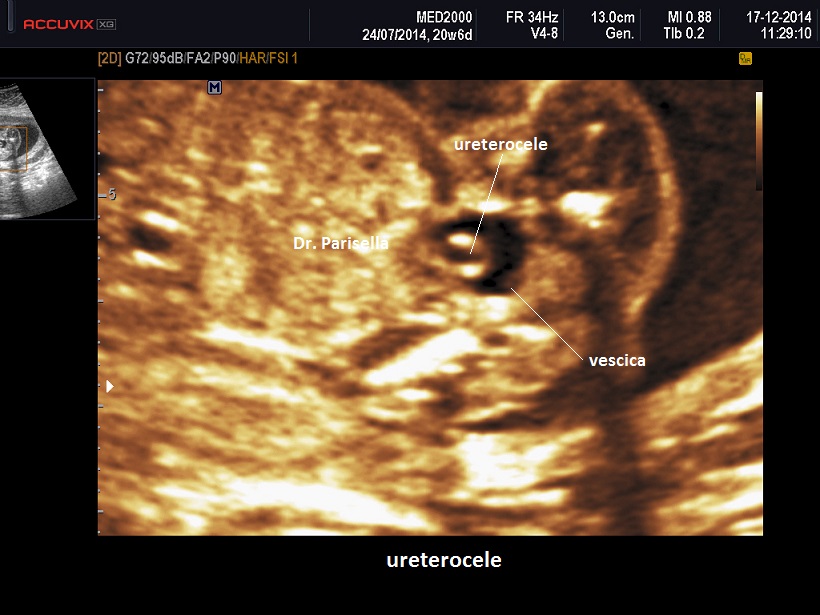

La forma semplice si presenta come una dilatazione cistica che occupa il lume vescicale.

Se l'ureterocele occupa tutta la vescica la diagnosi può essere impossibile in quanto viene a mancare l'immagine caratteristica che lo distingue: formazione cistica nel lume vescicale.